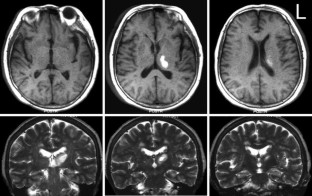

Two patients with isolated thalamic agraphia are described. Both showed kanji (Japanese morphograms) agraphia due to impaired character recall, grapheme deformity and micrographia (progressive reduction in character size during writing) after a lesion that involved the ventral lateral and ventroposterolateral nuclei. Single photon emission computed tomography with a 99mTc-ethylcysteinate dimer revealed hypoperfusion in the left precentral gyrus (Brodmann Area 6) and anterior supramarginal gyrus in both. Six months later, the extent of blood flow reduction decreased in the supramarginal gyrus in both patients and the precentral gyrus in patient 1. By this time, the writing impairment improved to nearly the normal range. Our study suggests that kanji agraphia (corresponding to lexical agraphia in Western countries) with poor grapheme formation and micrographia arises from a lesion in the ventral lateral and ventroposterolateral nuclei in the left thalamus. The accompaniment of poor grapheme formation and micrographia may reflect disruption of the cortico-subcortical motor circuit involving the putamen, thalamus, premotor cortex and sensorimotor cortex. It is also suggested that multiple cortical sites can be a target for secondary dysfunction that yields agraphia in a thalamic lesion, and that the recovery of reduced cortical blood flow does not always proceed in parallel with that of agraphia.

Fig. 2